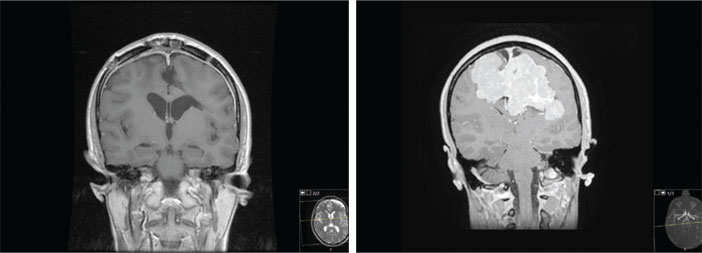

وأوضح د. الدهش أن المريضة كانت تشكو من صداع حاد وعدم قدرة على التركيز وضعف عام، حيث لجأت لعدة مراكز صحية بحثاً عن سببٍ لهذه الأعراض، حتى تم تشخيصها بوجود ورمٍ كبير في الرأس يستدعي تدخلاً جراحياً في مركزٍ متخصص، وتم تحويل المريضة إلى مركز العلوم العصبية التابع للمؤسسة العامة لمستشفى الملك فيصل التخصصي ومركز الأبحاث بالرياض، لإجراء المزيد من الفحوصات الدقيقة.

وأضاف أنه بعد إتمام الفحوصات والأشعة التشخيصية كافة في وقتٍ قياسي، تم تحليل الورم بشكلٍ دقيق واتضح أنه من الأورام التي تنشأ غالباً في جدران الشعيرات الدموية، ولا يتسبب بظهور أي أعراض أو علامات مَرضية في مراحله المبكرة، بل يتفاقم ويزداد سوءاً بزيادة حجمه وتأثيره على المناطق المجاورة له، كما يَصعب تشخيصه نظراً لاحتمالية عدم تمييزه عن أنواع أخرى من الأورام.

ووصف الدكتور أن التدخل الجراحي لاستئصال هذا الورم يُعد أمراً ليس بالسهل نظراً لحجمه الكبير ولوجوده بالقرب من منطقة حساسة جداً في الدماغ، مما يزيد من نسبة تعرض المريضة لمخاطر محتملة، كما أن النزيف من الورم يُعيق استئصاله بشكلٍ كامل نظراً لطبيعة الورم الدموية الأمر الذي يُعرض المريضة إلى نقل دم بكميات كبيرة، مما يُقلل من نسبة نجاح العملية الجراحية باستئصال الورم خلال عملية واحدة بدون مضاعفات التي تتراوح ما بين 40 - 50 %.

وطمأن الدهش أنه بعد إنهاء العملية التي استغرقت 14 ساعة، والتي تكللت بالنجاح حيث تم استئصال الورم كاملاً، وخروج المريضة إلى منزلها بعد مرور أربعة أيام من خضوعها للجراحة دون مضاعفات تُذكر وبصحة جيدة من فضل الله، مما يؤكد على أهمية التدخل الجراحي المبكر والمُوصى به لمثل هذه الحالات.